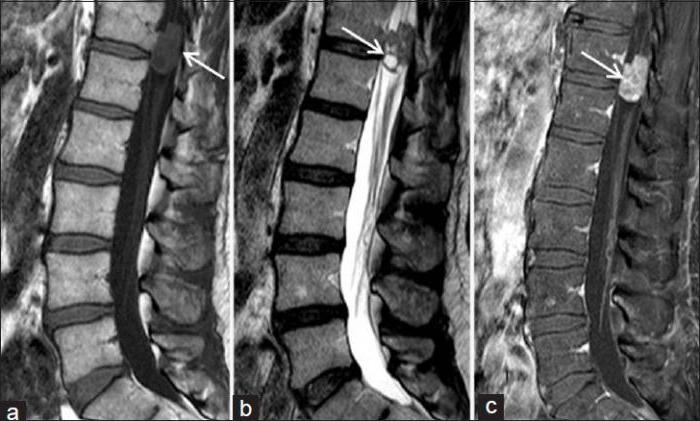

Остеохондрома в крестцовом отделе позвоночника

Остеохондрома

Остеохондрома – доброкачественное образование, которое формируется вместе с развитием скелета. Поражает детей и молодых людей в возрасте от 10 до 25 лет. Размер остеохондромы достигает 12 см. Не доставляет никаких неудобств, пока имеет небольшие размеры. По мере роста воздействует на сосуды и нервные окончания. При пальпации обнаруживается плотное, безболезненное образование. Кожные покровы в этом месте не гиперемированы, местная температура держится в норме.

Остеохондрома – это доброкачественная шишка на спине на позвоночнике, образовавшаяся из костной ткани. Диагностируется в возрасте 10-ти – 25-ти лет.

Причиной формирования шишки на позвоночнике у ребенка или более взрослого человека могут служить:

- врожденные аномалии костей;

- влияние лучевой терапии, проведенной в детстве;

- наличие остеохондроматоза.

Симптомы обычно отсутствуют. Можно случайно прощупать шишку на спине. Если она сильно разрастается, то сдавливает нервы, мышечную ткань. Вследствие этого наблюдаются различные проблемы с двигательной активностью, чувственностью и пр. Имеют место переломы, инфаркты, тромбозы. Шишка на спине не болит.

Лечат остеохордому ортопеды – хирургически. Показан радикальный метод тогда, когда опухоль существенно деформирует скелет и имеет большой размер.

Наркоз предварительно делается общий. После специалист удаляет образование и основание ножки. От костной пластики можно воздержаться.